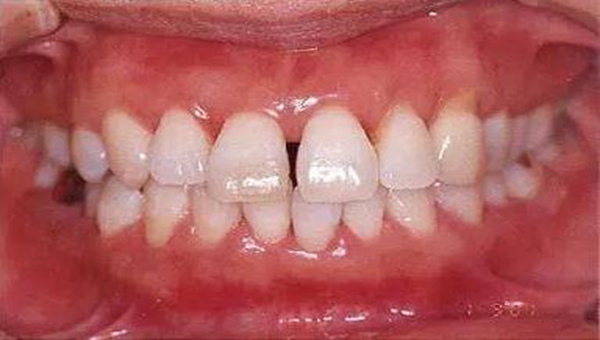

●參考病例② 25歲女性

25歲女性。菌斑控制狀態(tài)不好。齦溝除磨牙處外全在3mm以下,X光照片上左上、右下、左下的第一磨牙上有垂直性骨吸收。這個(gè)病例是參考病例①10年前的狀態(tài),是典型的侵襲性牙周炎局部型。